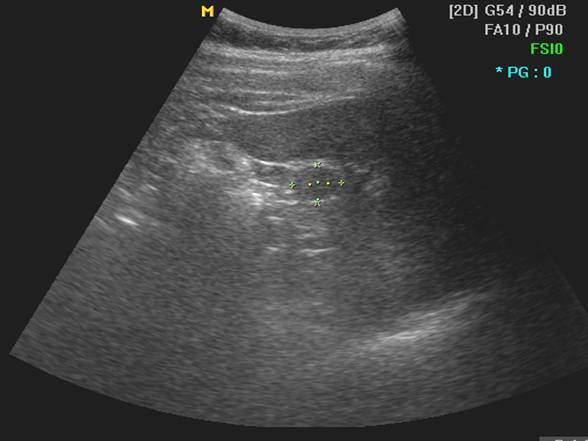

2 正常脾声像图